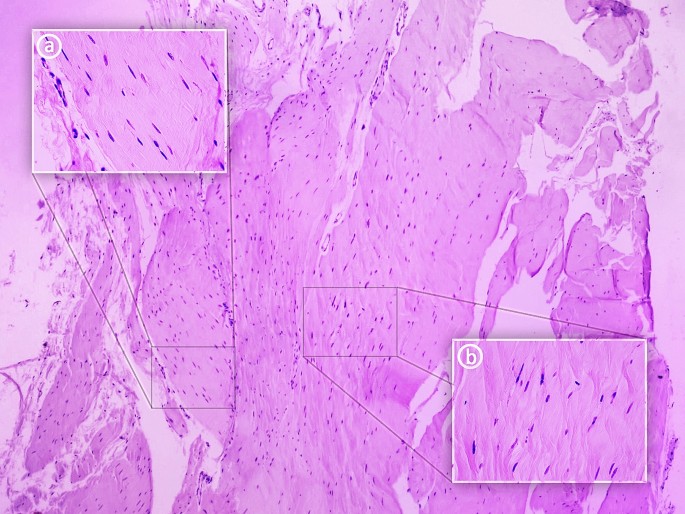

Most connective tissue fibers are visible in one direction. Figure 3 shows the nuclei of connective tissue cells. A number of unstained spaces can be seen: these probably resulted from post-mortem tissue lysis and sample preparation. An image at 25 × magnification is presented together with close-ups at 400 × (a and b).

Figure 3a. 400 × magnification: An approximation of a fragment of the PLT can be seen, indicated by the course of the collagen fibers. The fibroblasts forming the parallel fibers contain elongated and flattened nuclei. An important feature of the architecture of the indicated tissue is that a small amount of basic substance can be seen between the collagen fibers. These qualities are all characteristic of tendons.

Figure 3b. 400 × magnification: The photograph shows an approximation of a fragment of the PLT. The collagen fiber system differs from that seen in Fig. 2, the fibers being arranged in multidirectional waves rather than lying close and parallel to each other. Fibroblast nuclei are visible in different planes between the collagen fibers. Their shape is mainly ovoid. This arrangement of collagen fibers and the nuclei shape are characteristic of the PLT ligament14,15.

Histological examination revealed a tendon and ligament extending parallel to each other. In Fig. 3a a small amount of basic substance can be observed between the collagen fibers. Furthermore, flattened and elongated nuclei are visible in the fibroblasts forming the parallel and closely-packed bands of collagen fibers constituting the PLT. These features imply that a tendon-like tissue is present in the PLT structure14. However, in Fig. 3b, the tissue is characterized by spheroidal fibroblasts and their mostly ovoid nuclei located between the fibers, which are arranged in multidirectional waves. This histological texture is more typical of ligaments15.